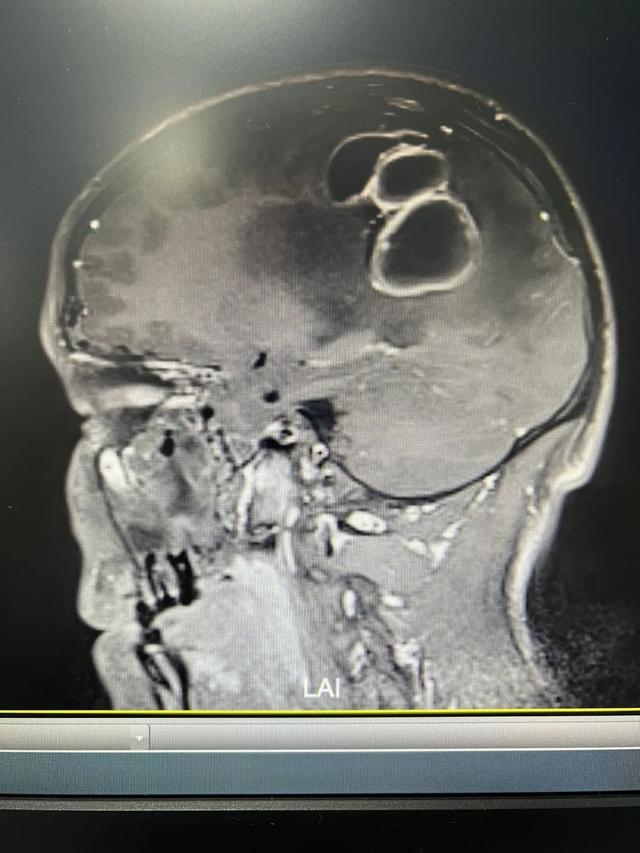

张眉了解了病史后,立即为小刘安排查,发现他右上肢肌力只有Ⅱ级,而且有轻度面瘫现象,迅速联系CT室为其做了头颅CT检查显示:“左侧顶枕叶异常密度影,伴周围脑水肿,脑中线右偏,建议MR(磁共振)平扫及增强检查”。张眉立马安排小刘住院治疗。

结合磁共振等影像学检查结果,小刘的颅内占位被确诊为脑脓肿,虽然没有肿瘤那么凶险,但对脑组织的压迫非常明显,需采取有效手术方式治疗。

手术过程很顺利,通过术前CT立体定向技术精准定位脓腔位置后,术中通过钻颅穿刺置入引流管抽吸出55ml脓性乳白色液体,立即将脓液进行病原学送检,同时术中充分冲洗脓肿腔,一个小时左右手术就结束了。